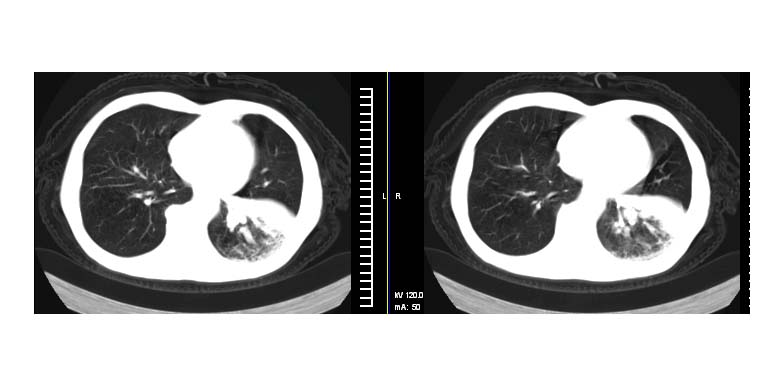

标题: CT11019:男性,66岁。发烧5-6天。治疗后无明显好转。 [打印本页]

标题: CT11019:男性,66岁。发烧5-6天。治疗后无明显好转。

考虑左肺下叶炎症合并叶间裂积液,建议抗炎治疗后复查

左侧胸廓偏小,左下梭形高密度影,考虑阻塞性肺炎.

斜肋积液

斜裂积液,炎症

明明是斜裂胸膜积液,为何都考虑阻塞性肺炎、肺不张(边缘内凹,而本例是外凸)。